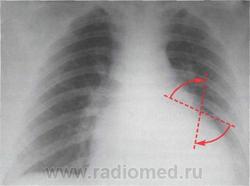

В переднезадней проекции на границе третьей и четвертой дуг левого контура сердца определяется «симптом коромысла» - асинхронные движения левого предсердия и левого желудочка, вызванные регургитацией крови в левое предсердие

Митральная недостаточность. Рентгенограмма сердца в переднезадней проекции. Схематически изображены движения «коромысла» на левом контуре сердца - между левым предсердием и левым желудочком

В левой передней косой проекции движения коромысла видны на заднем контуре сердца, верхний край которого образуется левым предсердием, а нижний - левым желудочком.